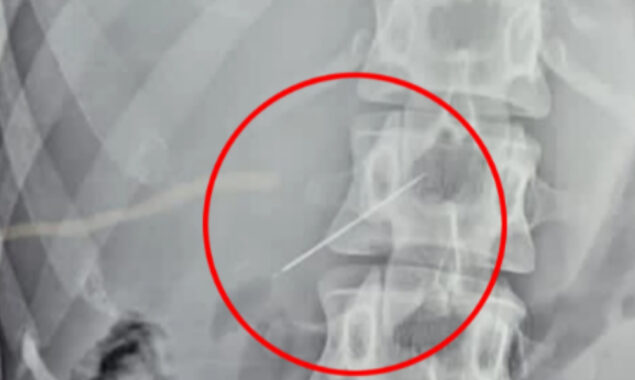

After being returned home after 10 days of several tests, including sonography, endoscopy, X-rays, and CT scans, a final ultrasound discovered the tiny needle embedded in her liver.

She was hurried into surgery once the needle was discovered to remove the object that was causing her anguish.

According to Jam Press, the procedure to remove the needle took two hours and utilised keyhole surgery, which requires only a small opening.